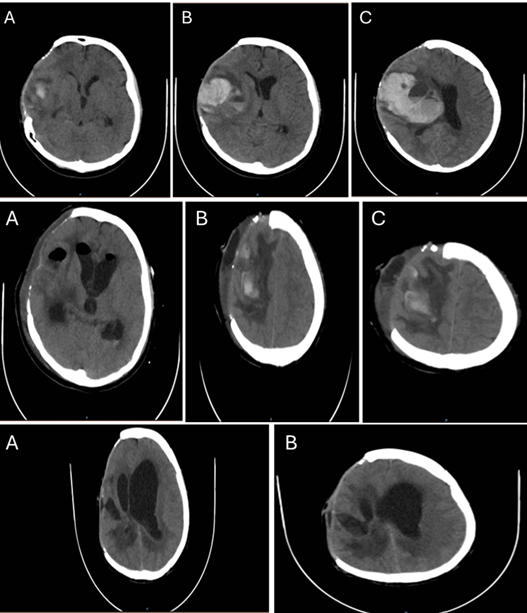

Intracranial complications in dengue fever are uncommon but have been increasingly reported in severe cases. Dengue fever is a mosquito-borne viral illness caused by the dengue virus, which usually presents mild symptoms such as fever, headache, and myalgia. In a minority of cases, the disease can progress to more severe forms characterized by plasma leakage, severe thrombocytopenia, and bleeding. Although neurological manifestations are not typical in dengue infections, factors such as severe thrombocytopenia and previous neurosurgical interventions may predispose patients to intracranial hemorrhagic events. This case report presents an 18-year-old female with a fatal intraparenchymal hemorrhage, occurring in the context of severe dengue and a history of prior post-traumatic craniectomy. This case illustrates how dengue-related thrombocytopenia and endothelial dysfunction can trigger catastrophic intracranial bleeding in areas of prior structural brain injury. Considering preexisting neurosurgical lesions as potential sites of secondary hemorrhage in dengue patients with severe thrombocytopenia.